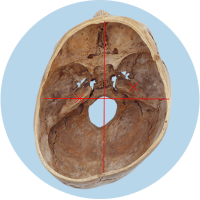

Le problème majeur réside dans la modification de la structure de la tête : la base du crâne devient asymétrique. Cela affecte principalement la position des oreilles (organes de l’équilibre), les articulations temporo-mandibulaires (malocclusion dentaire) et les vertèbres cervicales. La situation devient critique au plus tard lorsque les enfants se redressent à la fin de leur première année et développent une posture asymétrique de la colonne vertébrale.

Le déplacement des organes de l’équilibre est indiqué par les croix rouges.

Les informations erronées provenant des organes de l’équilibre déplacés ou du champ récepteur cervical influencent le traitement dans le cerveau et peuvent entraîner une mauvaise posture de la colonne vertébrale.